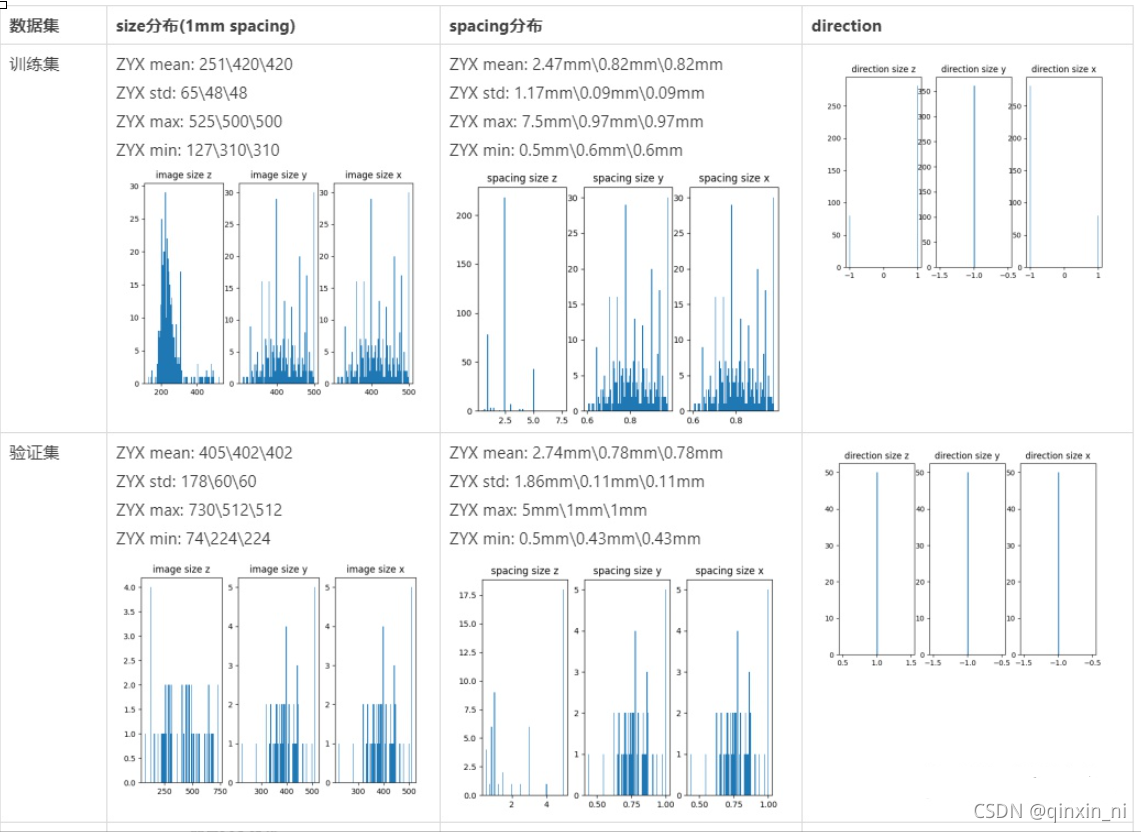

图像信息统计如下,训练集的图像大小呈现正态分布,验证集为均匀分布,平均大小为Z,Y,X=251,420, 420(训练集)、Z,Y,X=405,402,402(验证集), X、Y轴大小一致,但Z轴差异较大,主要是扫描范围差异较大导致的; 图像spacing平均为Z,Y,X=2.5, 0,8, 0.8mm,训练集和验证集基本一致; 训练集图像Z轴direction不一致,验证集图像direction为Z,Y,X=1,-1,-1,本文将所有图像的direction归一化为Z,Y,X=1,-1,-1,这样能够减少do redirection的次数。